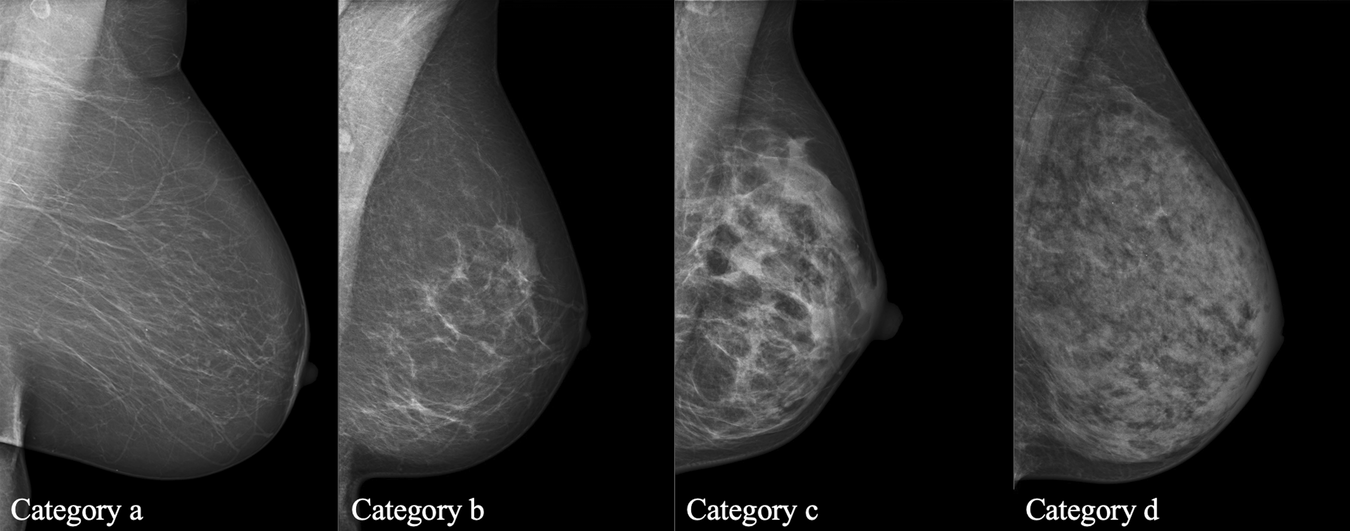

Fig. 1

Breast density categories according to the Breast Imaging Reporting and Data System (BI-RADS) from the American College of Radiology [57]. Depending on the breast composition, four different categories are identified: a entirely fatty; b scattered areas of fibroglandular density; c heterogeneously dense, which may obscure masses; and (d) extremely dense

The most common method of screening women for breast cancer is mammography, either offered by an organized program or in the form of opportunistic screening. In most European countries, mammographic screening programs include all women, with age being the only determinant: screening is offered starting at the age of 40–50 years until the age of 64–74 years or even illimitable if women are in good health (e.g., in Austria) at intervals of 1–2 years (3 years in the UK). Population-based effectiveness of mammography screening programs depend on high participation levels, and the European Guidelines for Quality Assurance in Breast Cancer Screening and Diagnosis recommend that at least 70–75% of a population participates in regular mammography screening [21]. Despite the overall survival advantages achieved with the use of mammographic screening, this “one-size-fits-all” approach is associated with several drawbacks, not least that mammography alone is not sufficient to achieve early diagnosis in the high-risk population. It has been reported that program sensitivities of 86–89% in women with largely fatty breasts drop to 62–68% in the case of women with dense breasts (Fig. 13) [22]. Considering that about 40–50% of women have dense breasts (heterogeneously and extremely dense breast), this represents a non-negligible issue. Breast density category after performing mammography screening should always be reported since this has important implications for the performance of supplemental and/or alternative imaging methods.